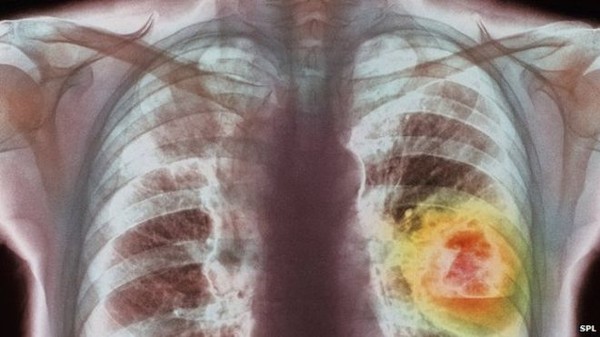

Bức tranh về Ung thư phổi

Trong đó ung thư phổi vẫn là căn bệnh ung thư ám ảnh nhất vì bệnh nhân phát hiện và tử vong chỉ trong thời gian rất ngắn, số ít mới có trường hợp kéo dài quá 5 năm.

Riêng năm 2018 có hơn 2 triệu người mắc bệnh ung thư này trên toàn thế giới chiếm 11,6 % trong số các bệnh ung thư nhưng tỷ lệ tử vong của ung thư phổi là 18,4 % với hơn 1,75 triệu người.

Ung thư phổi vẫn đứng đầu trong các bệnh ung thư

Ung thư phổi là nguyên nhân hàng đầu gây tử vong ở cả nam và nữ và là nguyên nhân hàng đầu gây tử vong do ung thư ở phụ nữ ở 28 quốc gia.